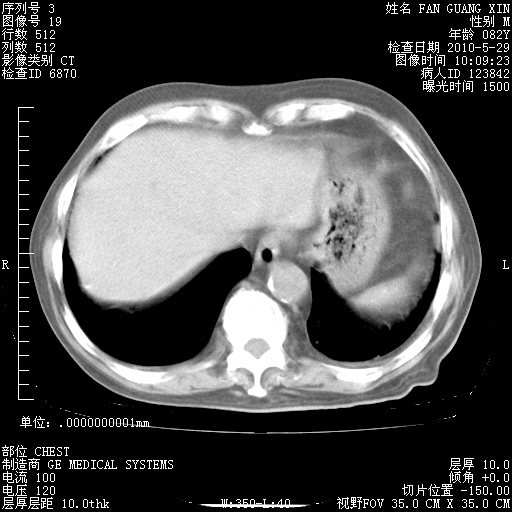

再治疗10天后的肺部CT

再治疗10天后的肺部CT 纵膈窗

阅读此次胸部CT,肺间质渗出性改变较入院时有吸收。目前从体温、白细胞、中性分叶明显增高,肯定存在细菌感染(发生医院感染哦,若无消化道及泌尿系统等感染的依据,肺部感染可能大)。若你院头孢哌酮舒巴坦钠耐药率较高,同意你的方案,若48小时体温仍高,可考虑使用碳青霉稀类抗菌药物,同时可予超声雾化、注意滴数时加大液体量。白蛋白33.30g/L较低哦,需加强营养等支持治疗。

从白细胞总数和中性比例看好像合并感染。肺部纹理好像比上次多,支气管炎?其他感染?